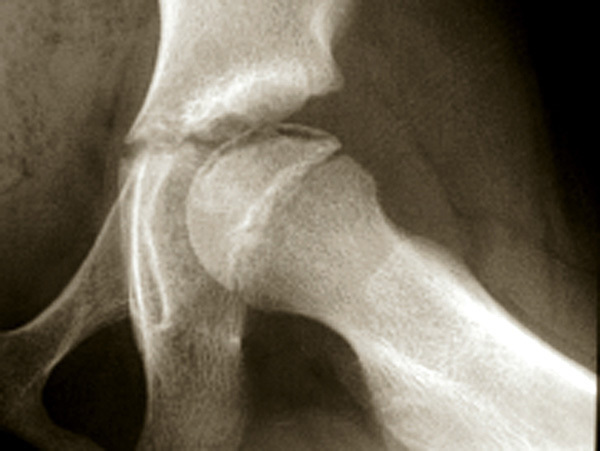

Ostéochondrite de hanche gauche au stade de début. Il s'agit d'une fracture sous-chondrale qui inaugure la douleur et donne un aspect radiographique en "coup d'ongle", c'est-à-dire un liseré noir juste sous l'os sous-chondral de l'épiphyse fémorale.